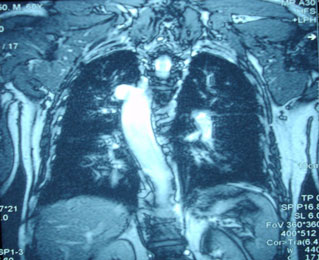

azygos vein (white arrow), Right sided aorta (white arrow head) MRI chest

shows fibrosis of mediastinum and right sided aortic arch